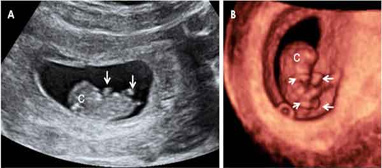

El feto con 9 semanas de gestación aún es diminuto, pero… ¡En una semana el bebé casi ha duplicado su talla! Ahora, en la semana 9 de embarazo, en la ecografía comprobamos que mide entre 17 y 22 milímetros. Y físicamente también ha cambiado mucho: la cola ha desaparecido y la cabeza se ha separado un poco del cuerpo gracias a un incipiente cuello que humaniza su silueta.